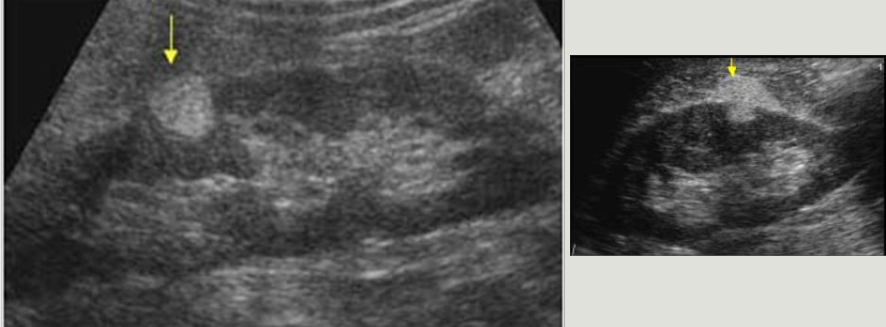

name that pathology -Dilation of the renal pelvis, calyceal structures, and infundibula by urine -Obstruction can be either intrinsic or extrinsic -Sonographic “hallmark” - splaying, spreading, or ballooning of the central echo complex -Dilated ureter helpful in differentiation

HYDRONEPHROSIS

28

hydronephrosis ratings Mild (aka pelvicaliectasis) ◦ dilatation of the renal pelvis with or without dilatation of the calyces (pelvicalyceal pattern is retained) ◦ Dilatation may also be noted in the extrarenal pelvis ◦ no parenchymal atrophy Moderate ◦ moderate dilatation of the renal pelvis and calyces ◦ blunting of fornices and flattening of papillae ◦ mild cortical thinning may be seen Grade 4 (severe) ◦ gross dilatation of the renal pelvis and calyces, which appear ballooned ◦ loss of borders between the renal pelvis and calyces ◦ renal atrophy seen as cortical thinning